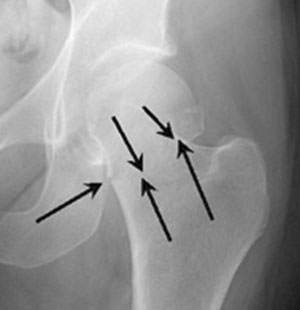

Вколоченный перелом шейки бедра у пожилых людей имеет минимальное количество симптомов, поэтому заподозрить патологию самостоятельно довольно сложно. И если для других видов повреждения шейки характерны такие диагностические признаки, как нарушение функции конечности, её укорочение, постоянное присутствие наружного поворота стопы, боль и развивающаяся гематома, то здесь единственный симптом – боль в паховой области. Да и сама боль носит мягкий характер, поэтому человек не спешит посетить врача.

Такое состояние получило название «вколоченный перелом» шейки бедра, при котором кости, сминаясь, вклиниваются друг в друга. При подобном состоянии есть небольшая вероятность сращения, но из-за отсутствия своевременной диагностики и необходимого лечения оно становится невозможным.

Симптомы перелома шейки бедра В некоторых ситуациях, например при вколоченном переломе без смещения, пациент может самостоятельно передвигаться, пусть и с трудом. Однако делать это категорически не рекомендуется. Также при переломе часто наблюдается наружная ротация ноги.